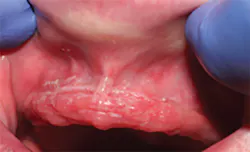

C. albicans hyphae thrive beneath a conventional acrylic maxillary denture despite pharmacotherapy and frequent denture disinfection.

Mandibular ridge photographed at the same appointment the maxillary ridge was photographed. Note absence of C. albicans hyphae.